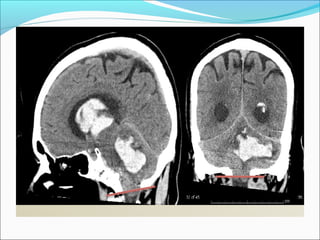

DESCENDING HERNIATION

Herniation:

Ascending Transtentorial

ļ‚—Cranial shift of

vermis and parts of

superomedial

cerebellar

hemisphere through

tentorium incisura

ļ‚— Compressed

superior cerebellar,

vermian cisterns and

forth ventricle

TONSILLAR HERNIATION

ļ‚—Inferior displacement of the cerebellar tonsils

through the foramen magnum

ļ‚—Can lead to posterior cerebellar artery infarction